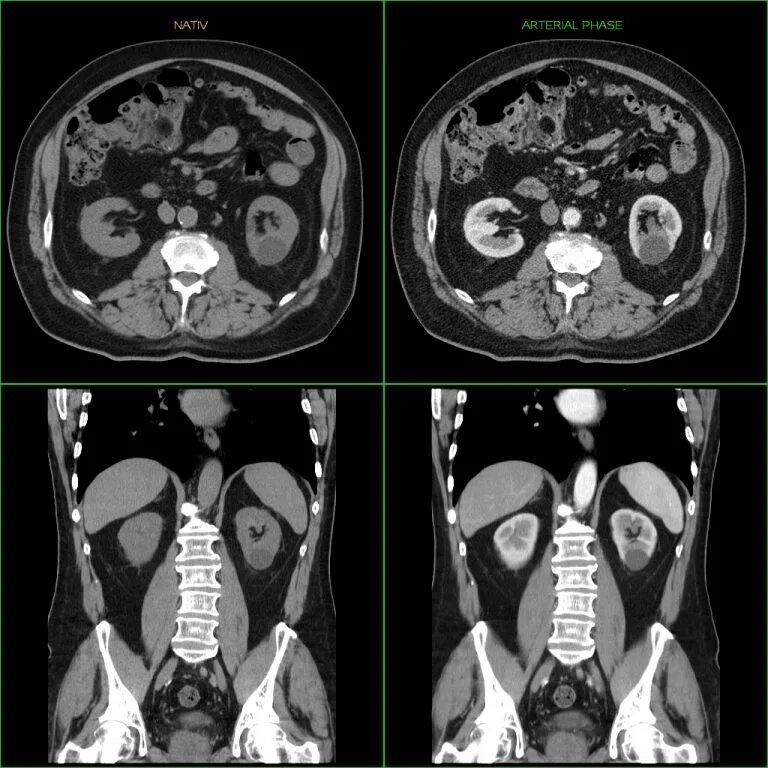

Как проходит кт всего тела